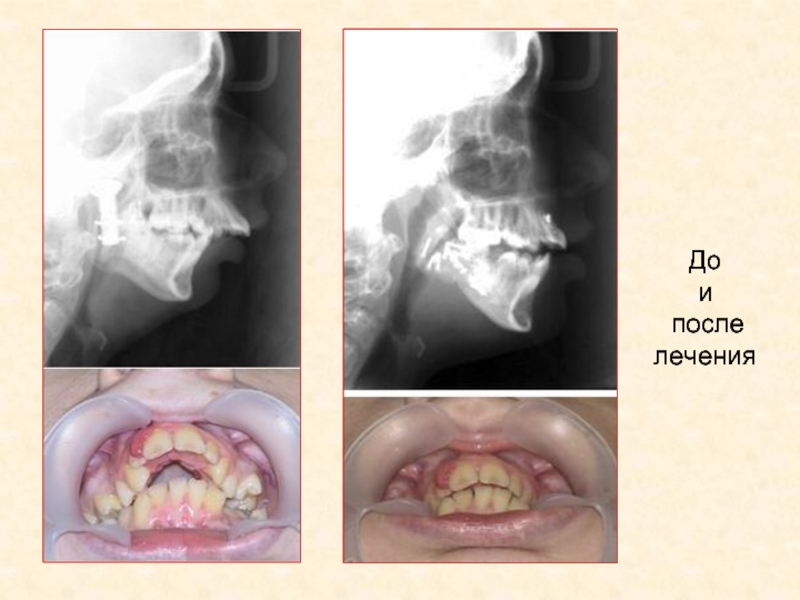

До

После

Слайд 39Анкилоз ВНЧС - до и после лечения

Слайд 40Анкилоз ВНЧС - до и после лечения

Слайд 41До и после лечения